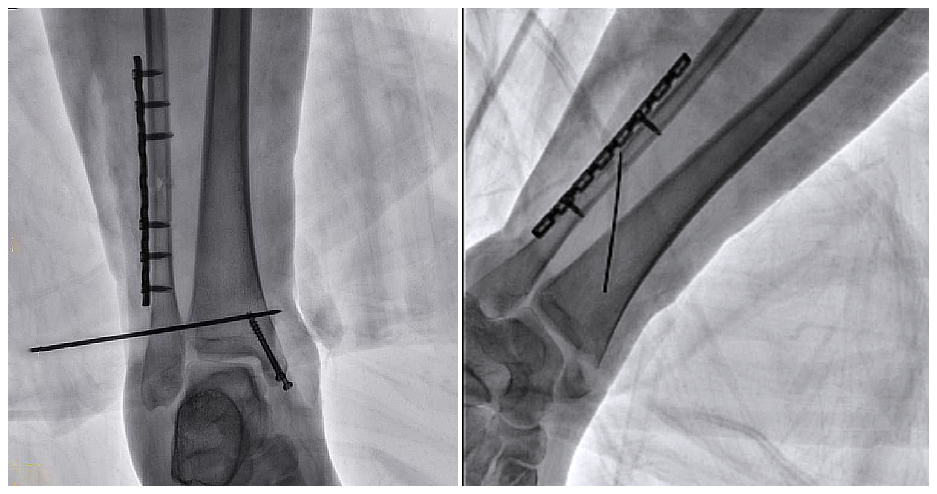

病例2 踝關(guān)節(jié)骨折復(fù)位(31歲)

在踝關(guān)節(jié)骨折復(fù)位手術(shù)中,用三維C可以更好地觀察骨折部位的復(fù)位情況:

正側(cè)位影像觀察脛腓聯(lián)合復(fù)位良好

從三維影像看,復(fù)位欠佳,貼合度不夠